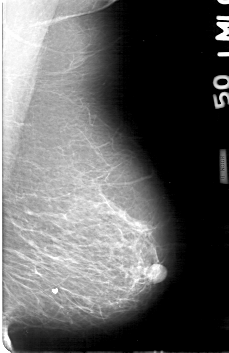

D_4170_1.LEFT_MLO

RIGHT_MLO LINES 5251 PIXELS_PER_LINE 3421 BITS_PER_PIXEL 12 RESOLUTION 43.5 OVERLAY

FILE: D_4170_1.RIGHT_MLO.OVERLAY

TOTAL_ABNORMALITIES 1

ABNORMALITY 1

LESION_TYPE CALCIFICATION TYPE AMORPHOUS DISTRIBUTION CLUSTERED

ASSESSMENT 0

SUBTLETY 2

PATHOLOGY BENIGN